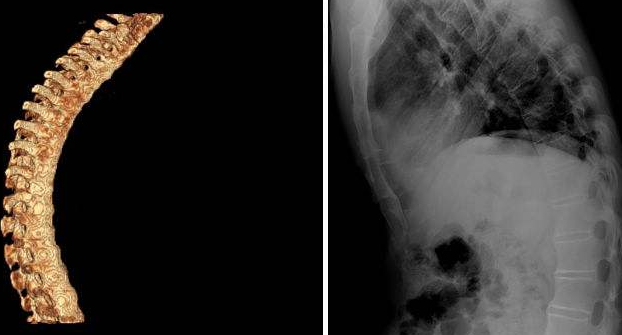

现如今,有不少人都患有强直性脊柱炎,得了这种病,会给患者的脊柱造成很大的伤害,严重时很可能会导致患者难以活动。所以,如果患了强直性脊柱炎需要及时治疗。下面贵阳治疗强直性脊柱炎专科医院就为大家介绍一下强直性脊柱炎的非手术治疗方法。